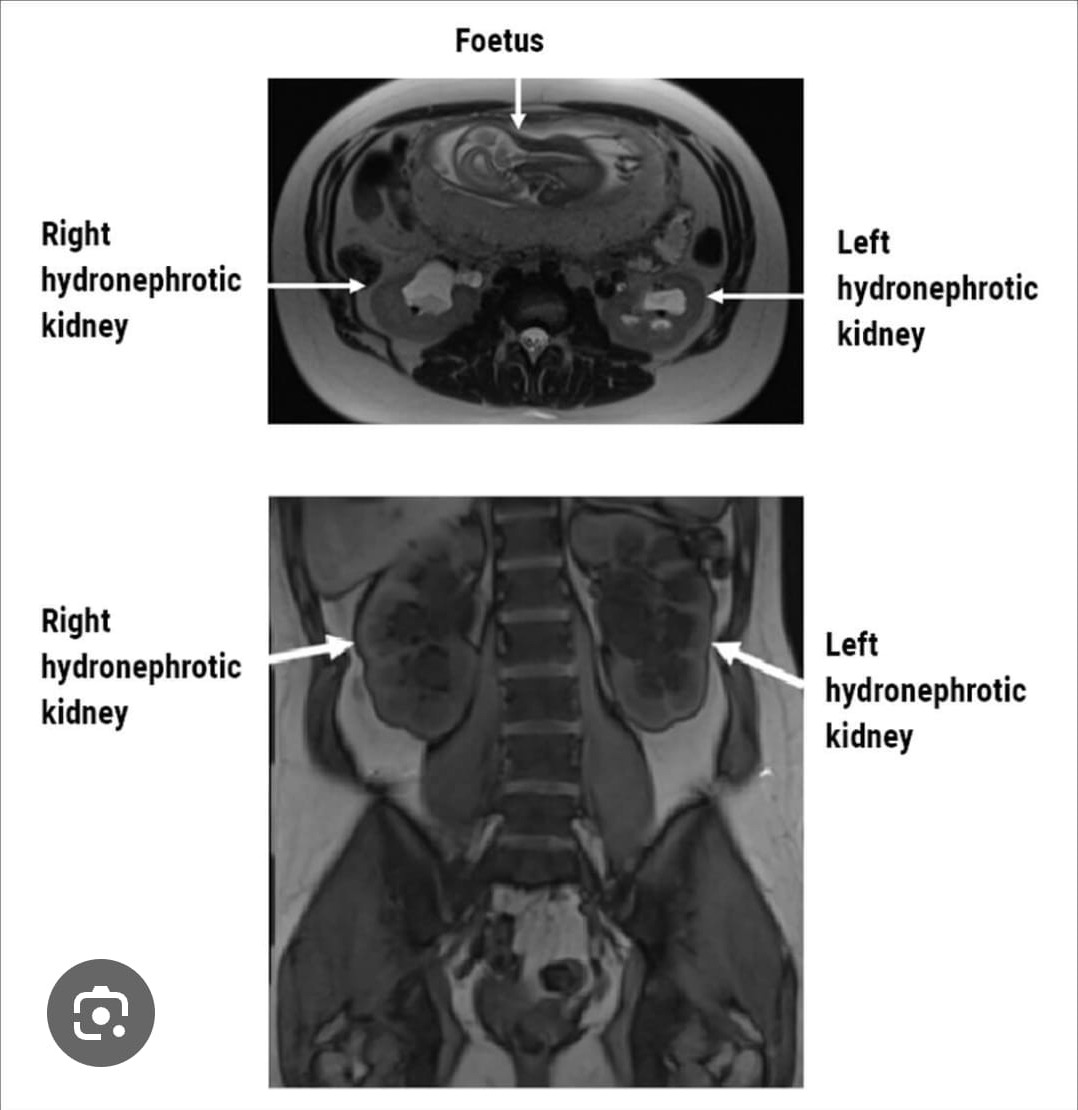

Why Kidney Stones Can Happen During Pregnancy Pregnancy increases the risk because: Hormonal changes (especially progesterone) relax the urinary tract → urine flows more slowly. The growing uterus presses on the ureters. Increased calcium excretion in urine. Dehydration (common with nausea/vomiting). Symptoms Symptoms are similar to non-pregnant cases: Severe pain in the side or lower back (often one-sided) Pain that radiates to the lower abdomen or groin Nausea and vomiting Blood in urine Painful urination Urinary urgency Fever (this is urgent and requires immediate care) ⚠️ If there is fever, chills, or decreased baby movement, seek emergency care immediately. How It’s Diagnosed Because radiation should be avoided during pregnancy: Ultrasound is the first-line imaging test. MRI may be used if needed. CT scans are usually avoided unless absolutely necessary. Treatment During Pregnancy Most stones pass on their own. Conservative (most common approach) Hydration (IV fluids if needed) Pain control (pregnancy-safe medications) Monitoring baby and mother If the stone does not pass or infection develops Procedures that may be considered: Ureteral stent placement Nephrostomy tube Ureteroscopy (can be done safely in pregnancy in many cases) Shock wave lithotripsy is not used during pregnancy. Risks If untreated, kidney stones can increase the risk of: Urinary tract infection Kidney infection Preterm labor Rarely, kidney damage Prompt treatment significantly reduces these risks. When to Go to the ER Immediately Fever over 100.4°F (38°C) Uncontrolled pain Persistent vomiting Signs of preterm labor (contractions, fluid leakage) Decreased fetal movement (later pregnancy)